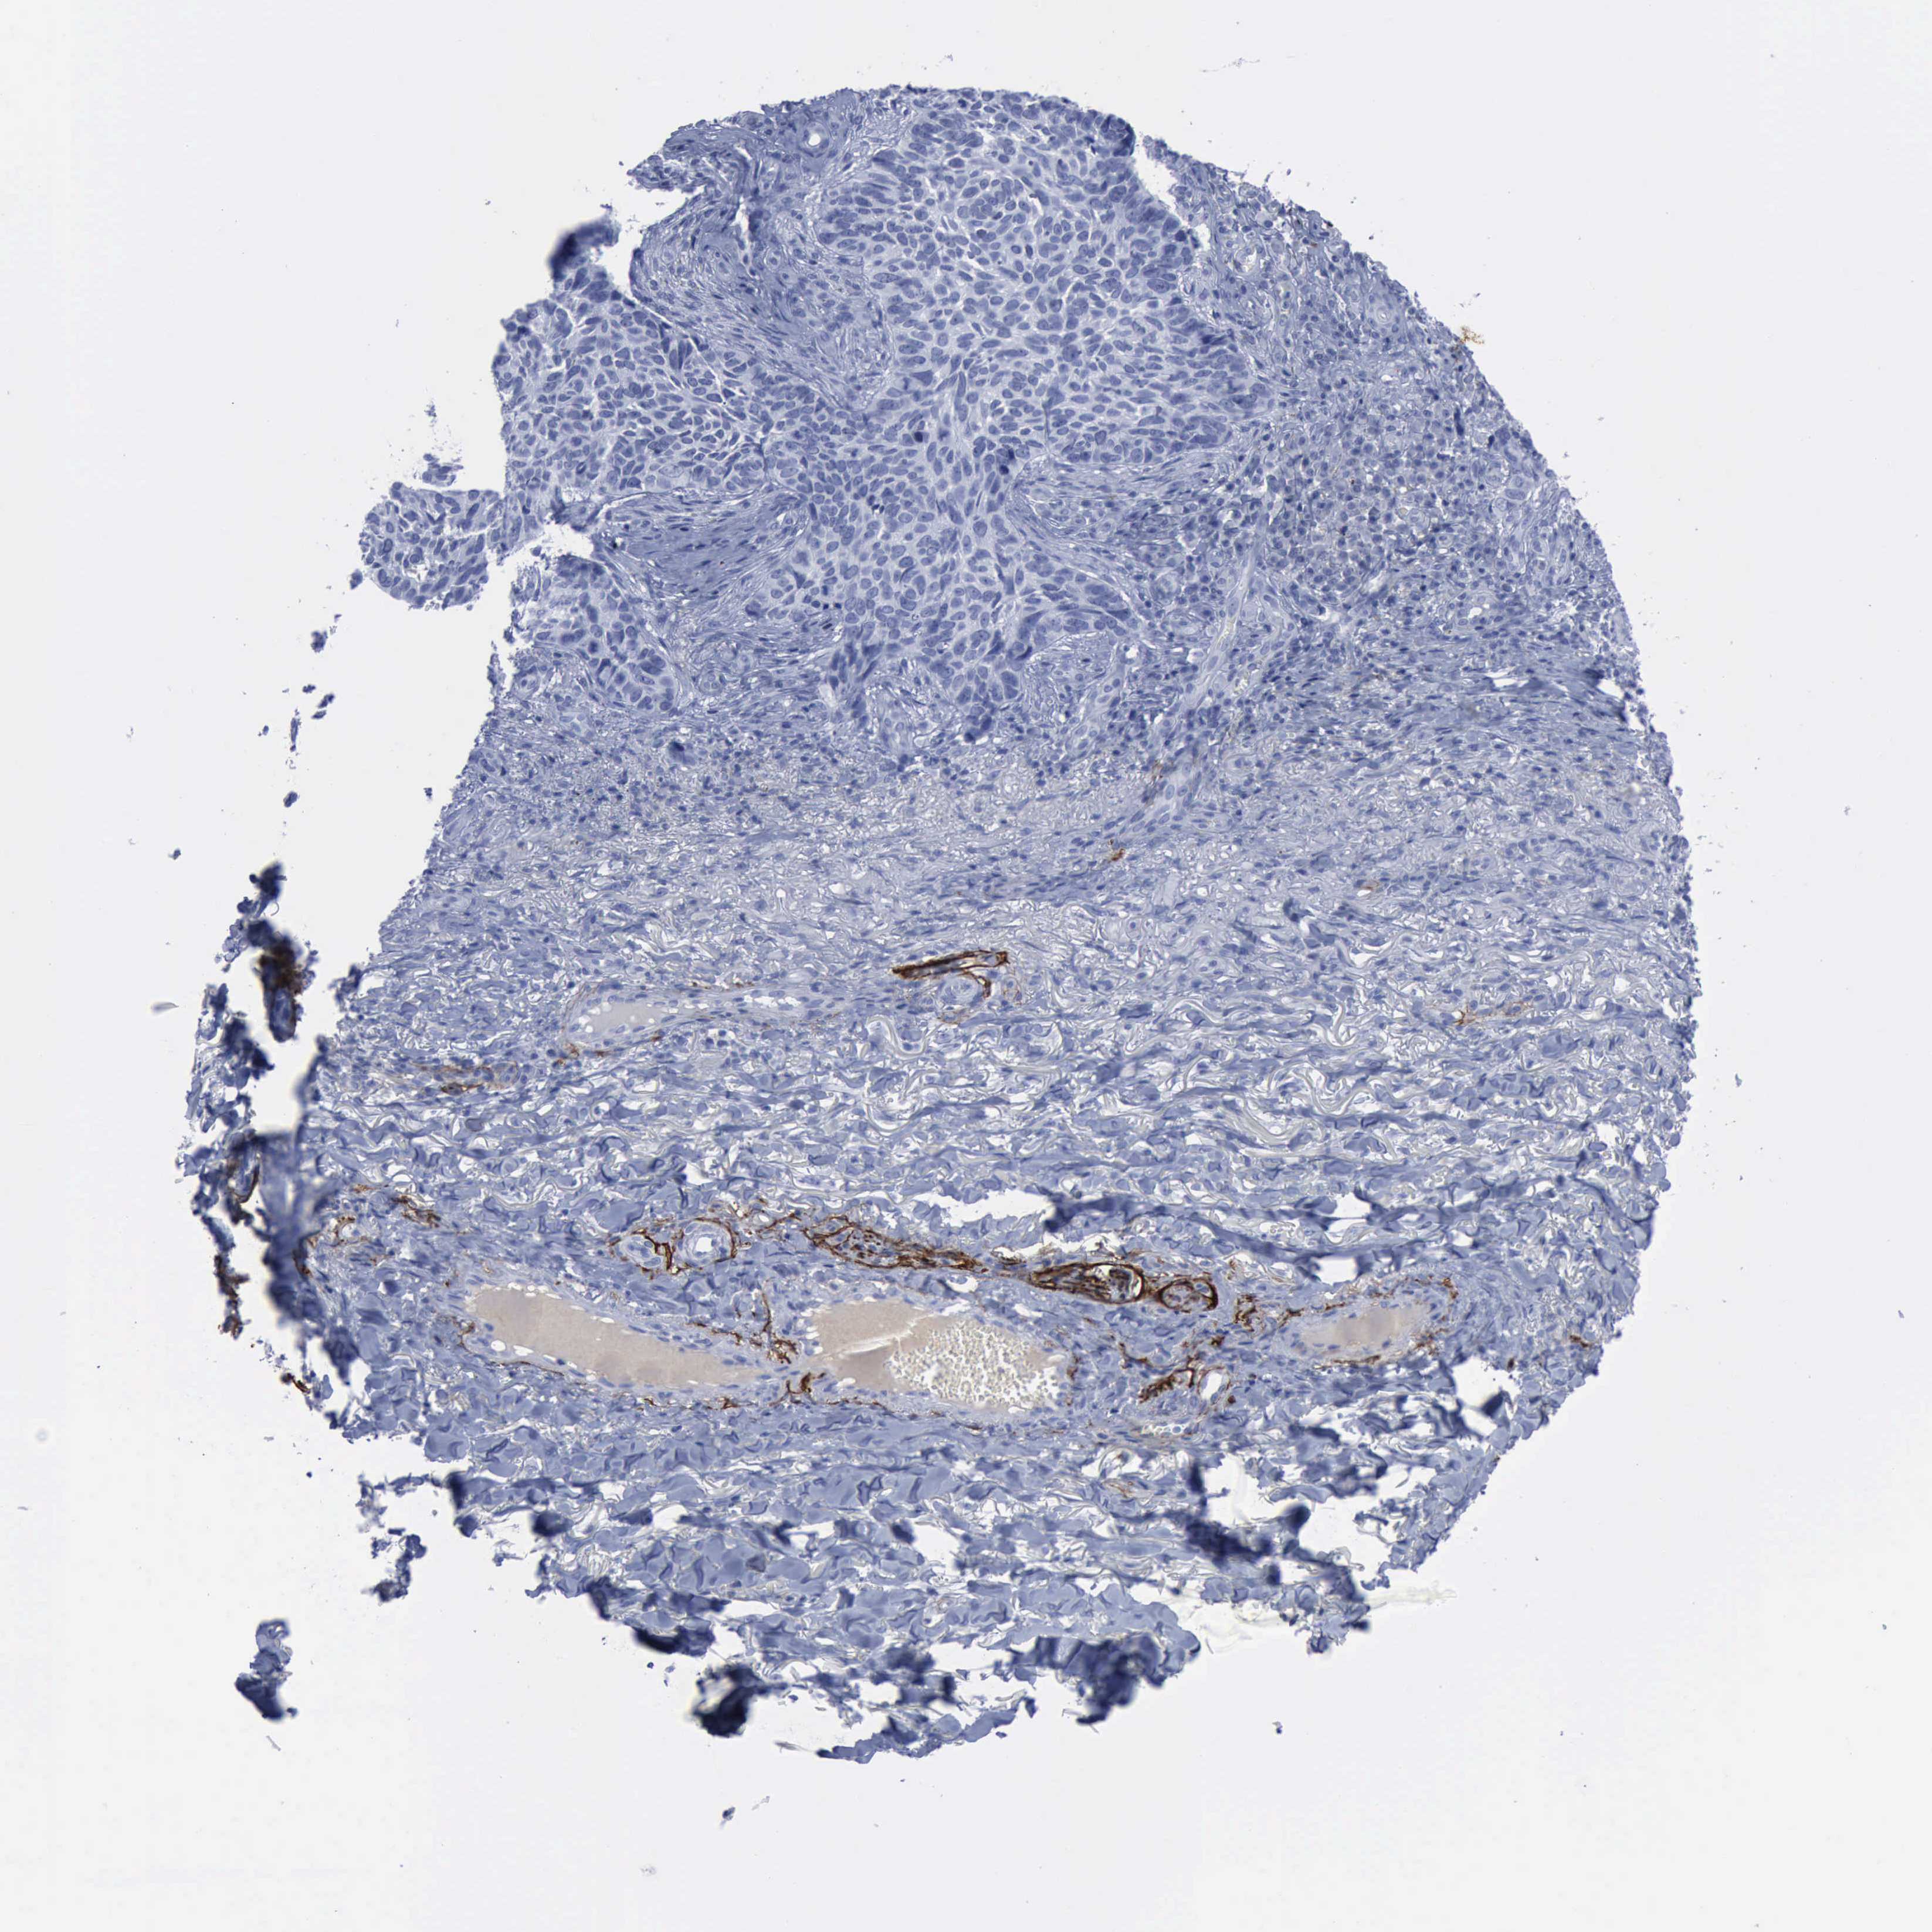

CANCER SKIN CANCER Show tissue menu

Basal cell and squamous cell cancer

SKIN CANCER - Protein expressioni

A mouse-over function shows sample information and annotation data. Click on an image to view it in a full screen mode. Samples can be filtered based on level of antibody staining by selecting one or several of the following categories: high, medium, low and not detected. The assay and annotation is described here.

Each image is clickable and will lead to virtual microscopy that enables deeper exploration of all samples and also displays staining intensity scores, fraction scores and subcellular localization as well as patient and tissue information for each sample.

Antibody CAB000143

Squamous cell carcinoma, NOS

Basal cell carcinoma